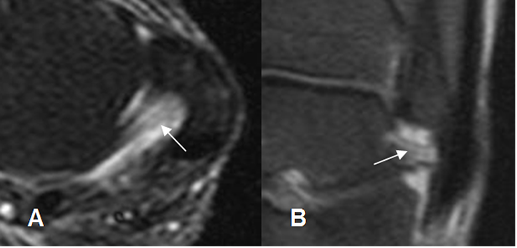

En los esguinces agudos grado I, se encuentra el ligamento íntegro, rodeado por líquido por edema o hemorragia y pérdida de los planos grasos. (Fig 60). En los grado II, el ligamento es irregular e hiperintenso, con cambios inflamatorios mas severos. (1, 12). (Fig 61, 62 y 63).

En los esguinces grado III, hay discontinuidad de las fibras por ruptura (1). Las rupturas completas del LPAA, se asocian siempre con abundante hemartrosis. (12). (Fig 64 A, 64 B y 65 C).

Fig 61. Esguince grado II.

A: RM axial y B: RM coronal en STIR. Fibras hiperintensas del LPAP por distensión, pero se conservan integras.

Fig 64 B. Esguince grado III.

RM axial en T2. Ruptura completa del LPAA, con líquido fuera de la articulación.

Fig 64 C. Esguince G III.

RM coronal en STIR. No visualización de los ligamentos peroneoastragalino, ni peroneocalcaneo, por ruptura completa.